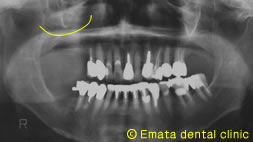

Before

奥歯の上には上顎洞という空洞(黄色の線)がありこのままではインプラントが上顎洞内に突き抜けてしまうためインプラントの手術ができません。